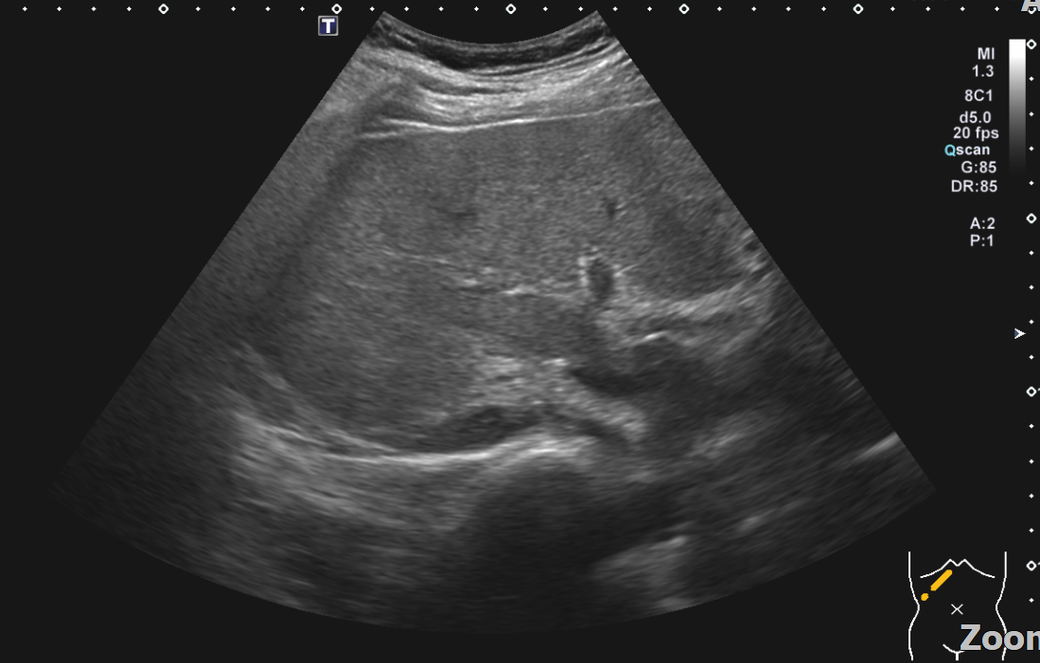

복부초음파 신장 물혹 보이나요? 사진올려봐요

신장물혹 0.6cm mri에는 나오는데 복부초음파에는 소견이없어서요

• 1번 째 사진

올려주신 사진 중 우측 신장이 찍힌 영상은 한 장이며 단면 영상만으로는 물혹 유무를 확인할 수 없습니다.